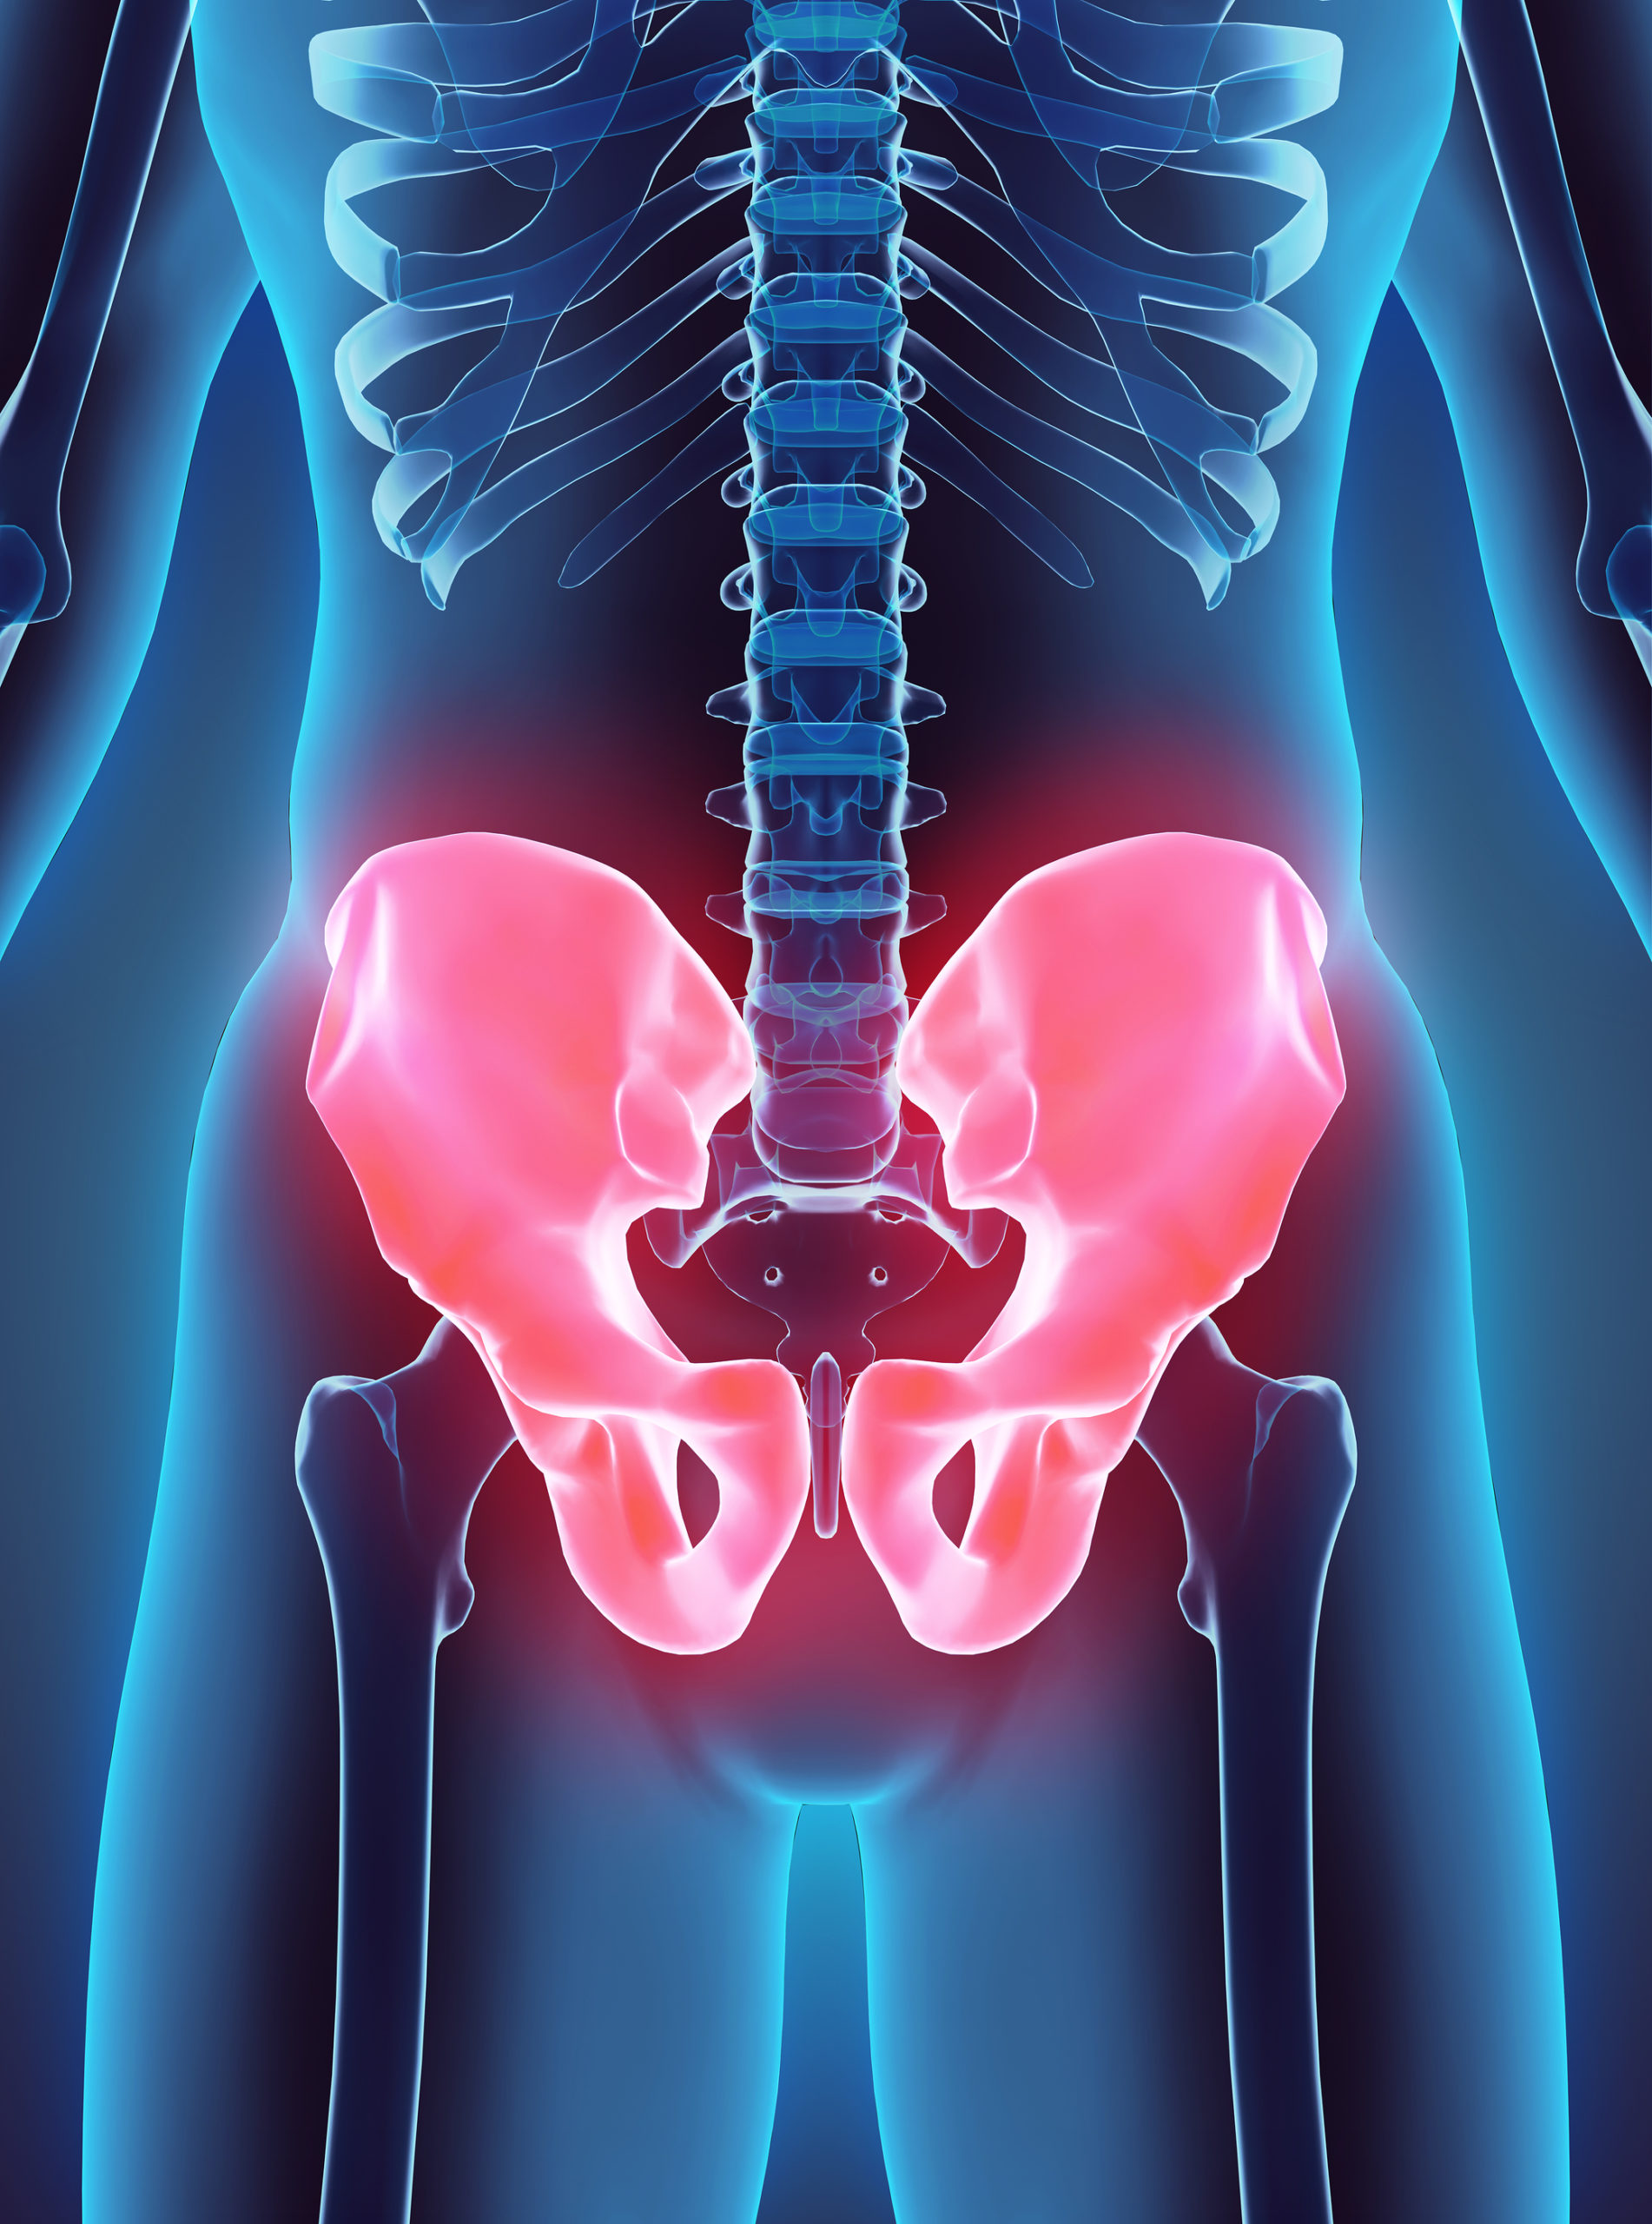

Hip bursitis, also called trochanteric bursitis, affects many people every day. It is characterized by pain and/or stiffness in the hip which is worsened with pressure, and potentially redness and swelling. The pain is caused by inflammation of the fluid-filled sacs, called bursae, which cushion the bones, tendons, and muscles near your joints. Normally part of a cushioning system to ease joint movements, inflamed bursae can make moving quite painful.

The hip is the largest and highest weight-bearing joint in the body, so it’s no wonder inflammation can occur around it. Where the femur (upper leg bone) meets the pelvis, a ball-and-socket joint sits which gives you your range of motion in your hip. It is held in place by large ligaments, muscles, and tendons, and coated in thick cartilage to make your everyday motions easy, and pain-free. However, problems such as trochanteric bursitis can arise and make movements quite painful. Inflamed bursae are further irritated by any hip movements around them, making hip bursitis a debilitating condition, especially for those who are physically active.